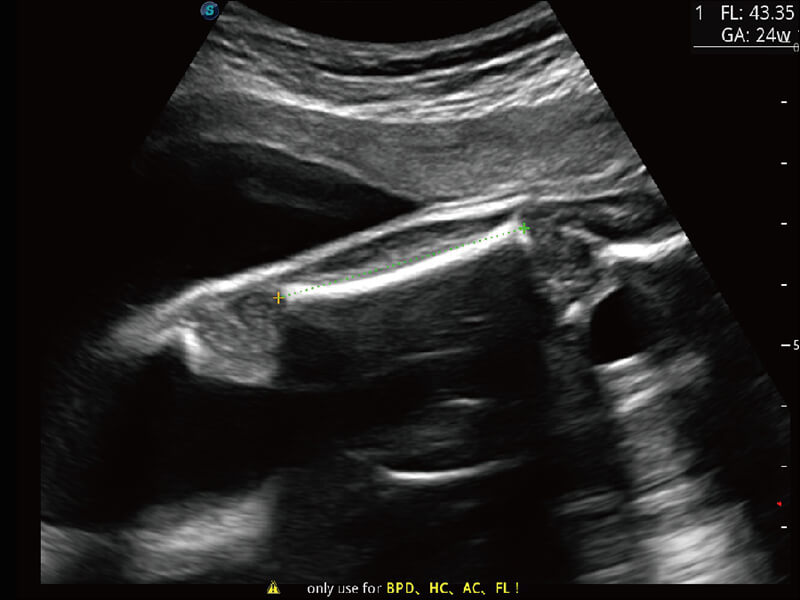

超宽频带技术,为容积成像带来优质的二维图像基础,为您呈现丰富的结构细节,栩栩如生地展示宝宝的宫内形态以及各种组织的立体结构。